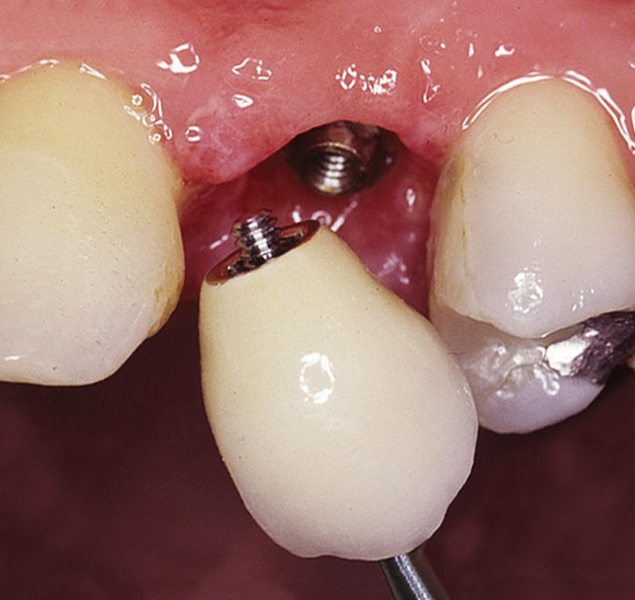

Protetické řešení může být pomocí můstku, který je kotvený na implantátech nebo pomocí jednotlivých korunek na implantátech.

V zásadě je možné do těchto můstků zařadit i přirozené zuby, zejména pokud je potřeba tyto zuby ošetřit proteticky - korunkami. Korunky nebo můstky mohou být na implantáty nacementovány nebo přišroubovány.